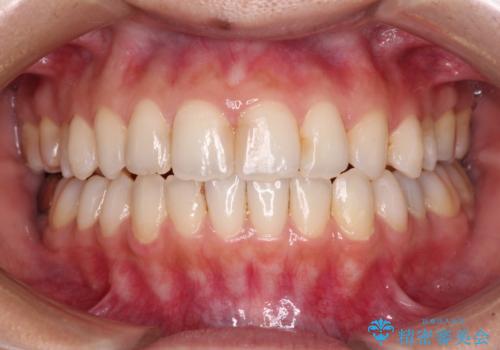

オープンバイトによる見た目を治したい インビザラインでの矯正治療

- オープンバイトのため、話しているときの見た目が気になるとのことで来院された患者様です。

下顎骨は左側にシフトしており、咬み合ったときには奥歯と前歯の一部しか接触していない状態でした。

骨格的な左右差は歯列矯正は改善できないため、上下歯列が全体的に接触することをゴールとしてインビザラインにて矯正治療を行うこととしました。

前歯のデコボコの解消と並行して上下の奥歯を圧下させるようにすることで、前歯を接触させるように計画しました。

上下の隙間に舌が入り込むことがオープンバイトの原因であったため、舌の筋肉のトレーニングも並行して行い、後戻りの抑制を図りました。